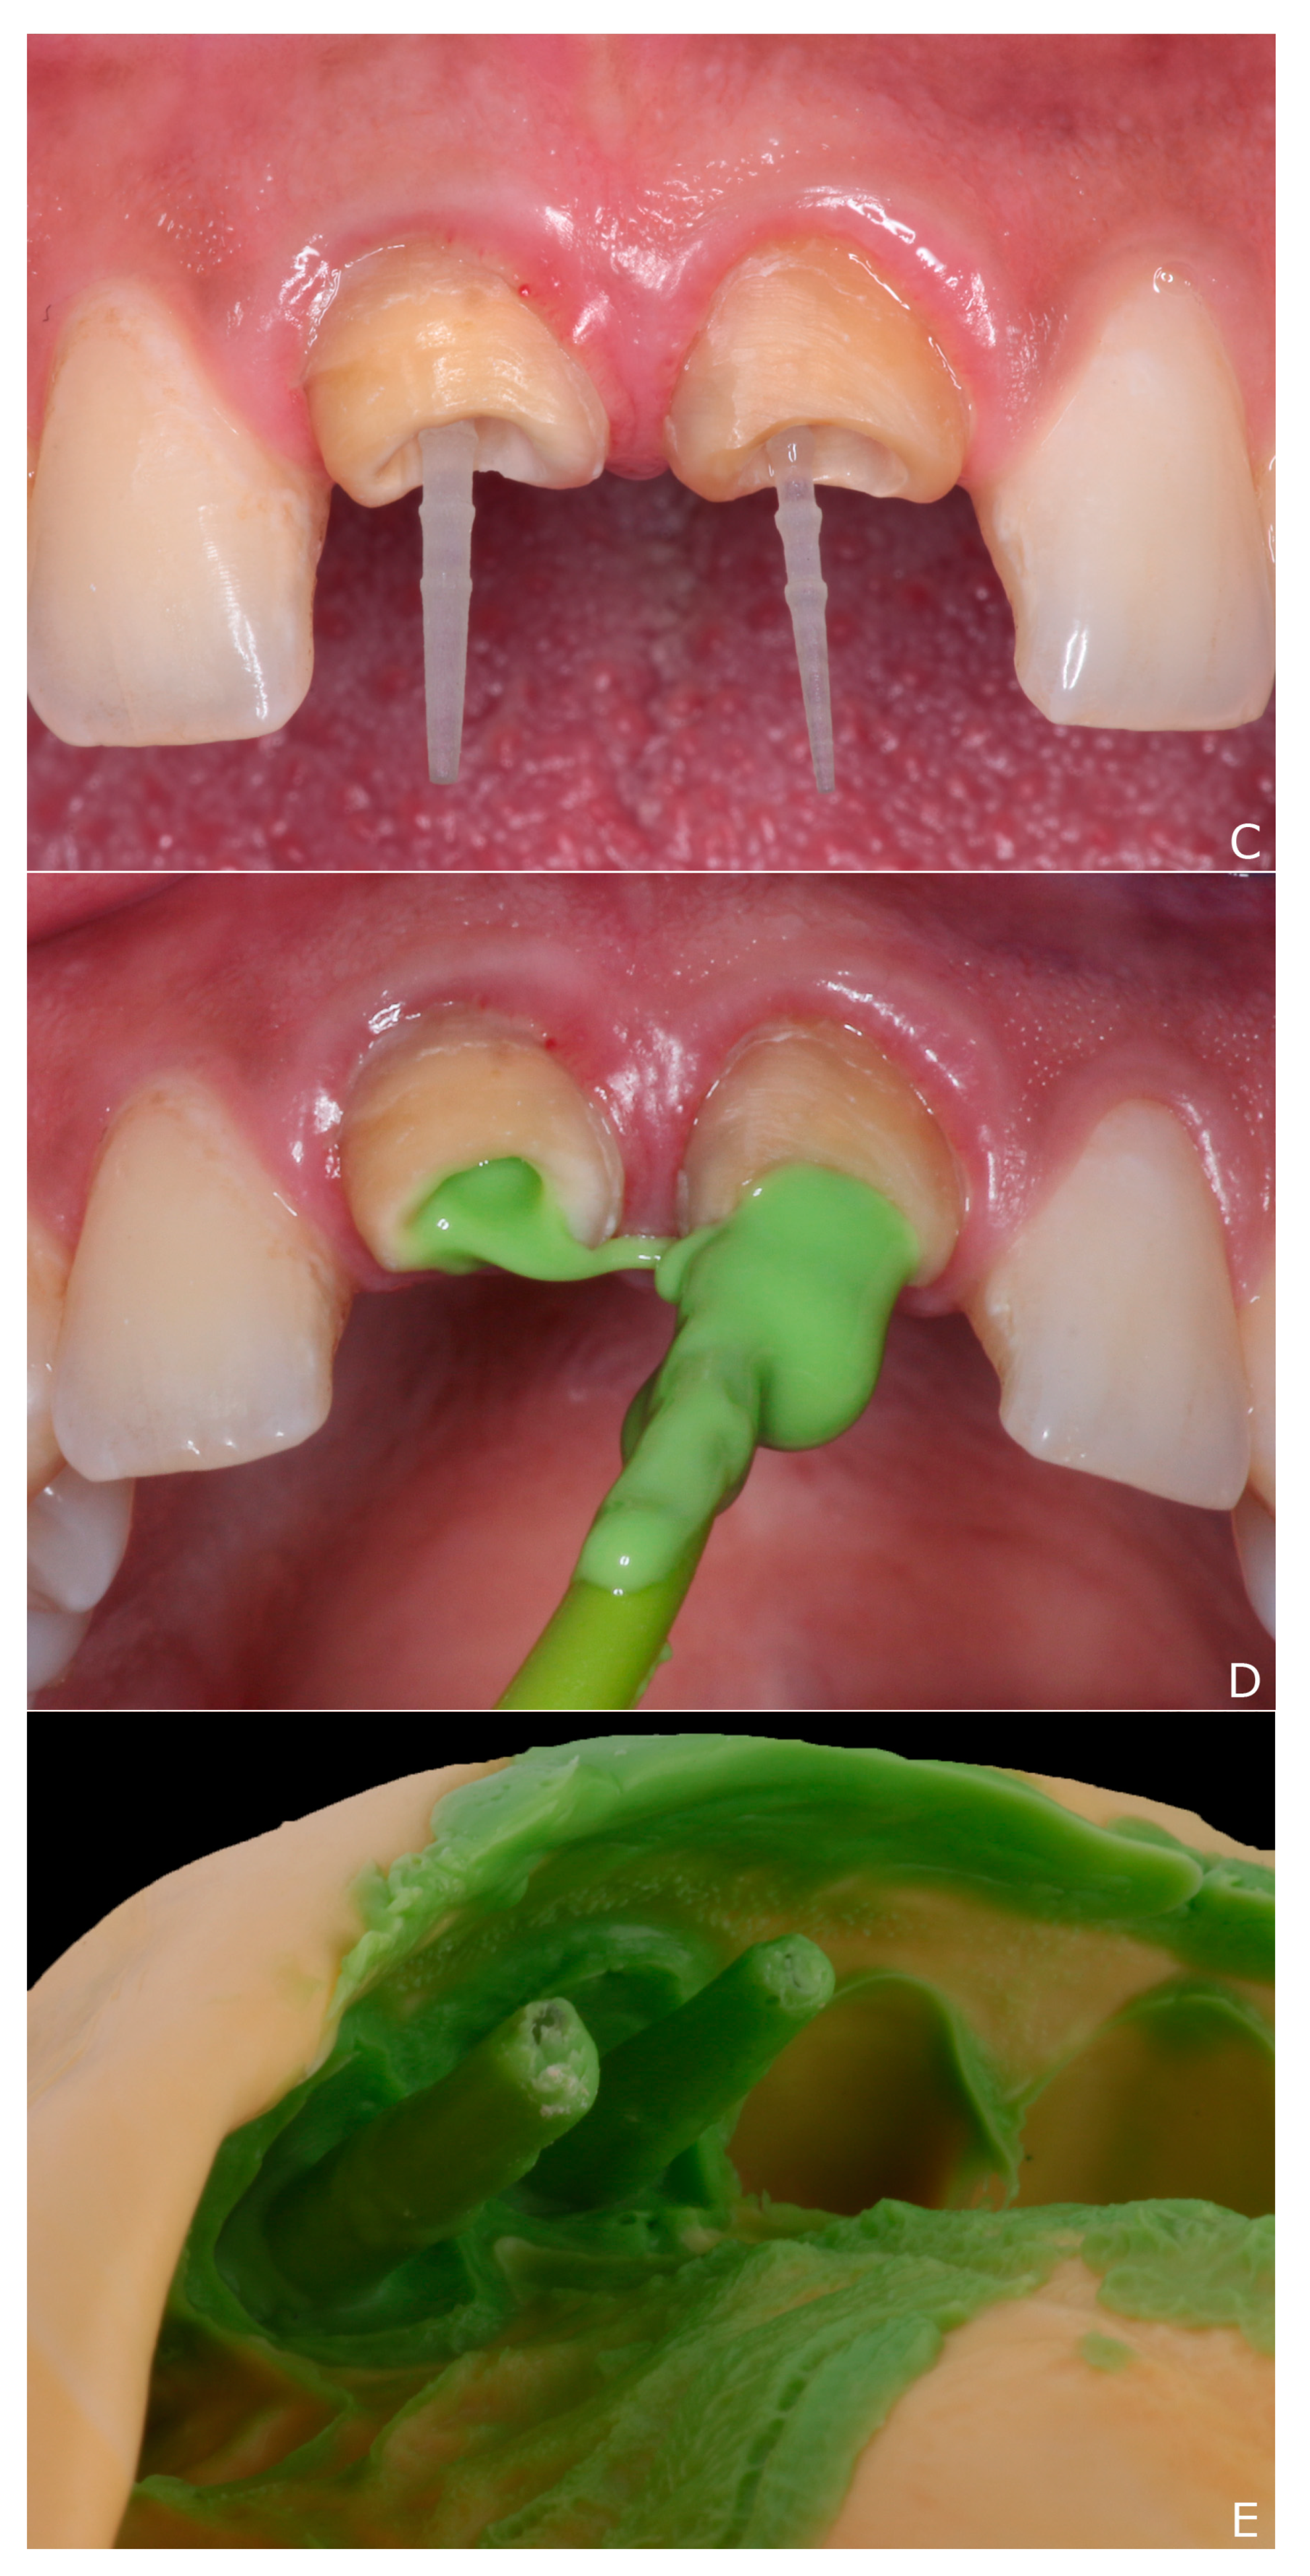

2. Clinical Report